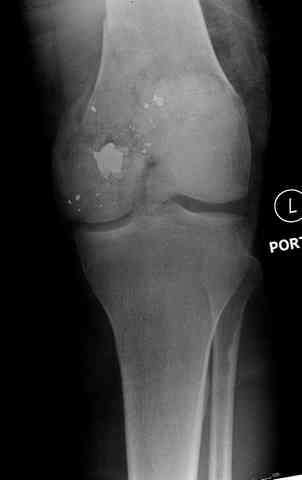

Небольшие входные пулевые раны до 1 см (см. на снимке) закрываются в течение нескольких дней самостоятельно даже без обработки. Раны более 3 см также не нуждаются в специальной обработке, и для самостоятельного закрытия ран бывает достаточной обычная обработка стенок раны "кюретажем".

Условием для обязательного удаления пули считаем ее внутрисуставное расположение из-за возможного сатурнизма, или когда во время операции она без труда удаляется, а также поверхностно расположена.

Здесь представлены несколько случаев лечения огнестрельного перелома

2 внутрисуставной перелом дистального бедра с удалением пули